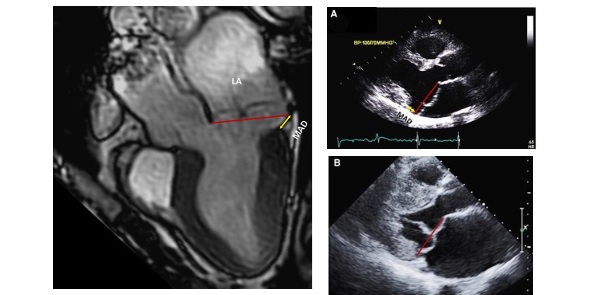

Пролапс створок мк

Пролапс створок мк 110 фотографий